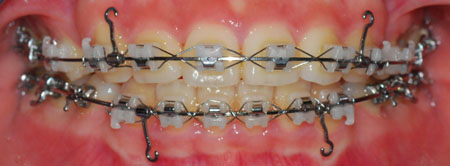

(19번째 교정 일기에서의 치아 상태)

많이 달라졌죠?

이제 발치공간을 줄이기 위해 고무줄을 더 열심히 걸어야 겠어욧!